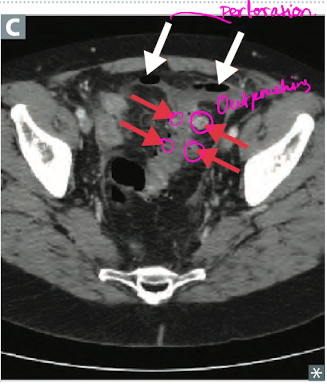

8

Q

What are the complications to diverticulitis?

A

Abscess, fistula, (colovesical fistula -> pneumaturia (stool and air in the urine), obstruction (inflammatory stenosis), perforation that can lead to peritonitis. Hematochezia is rare.

Treat with surgery and antibiotics.